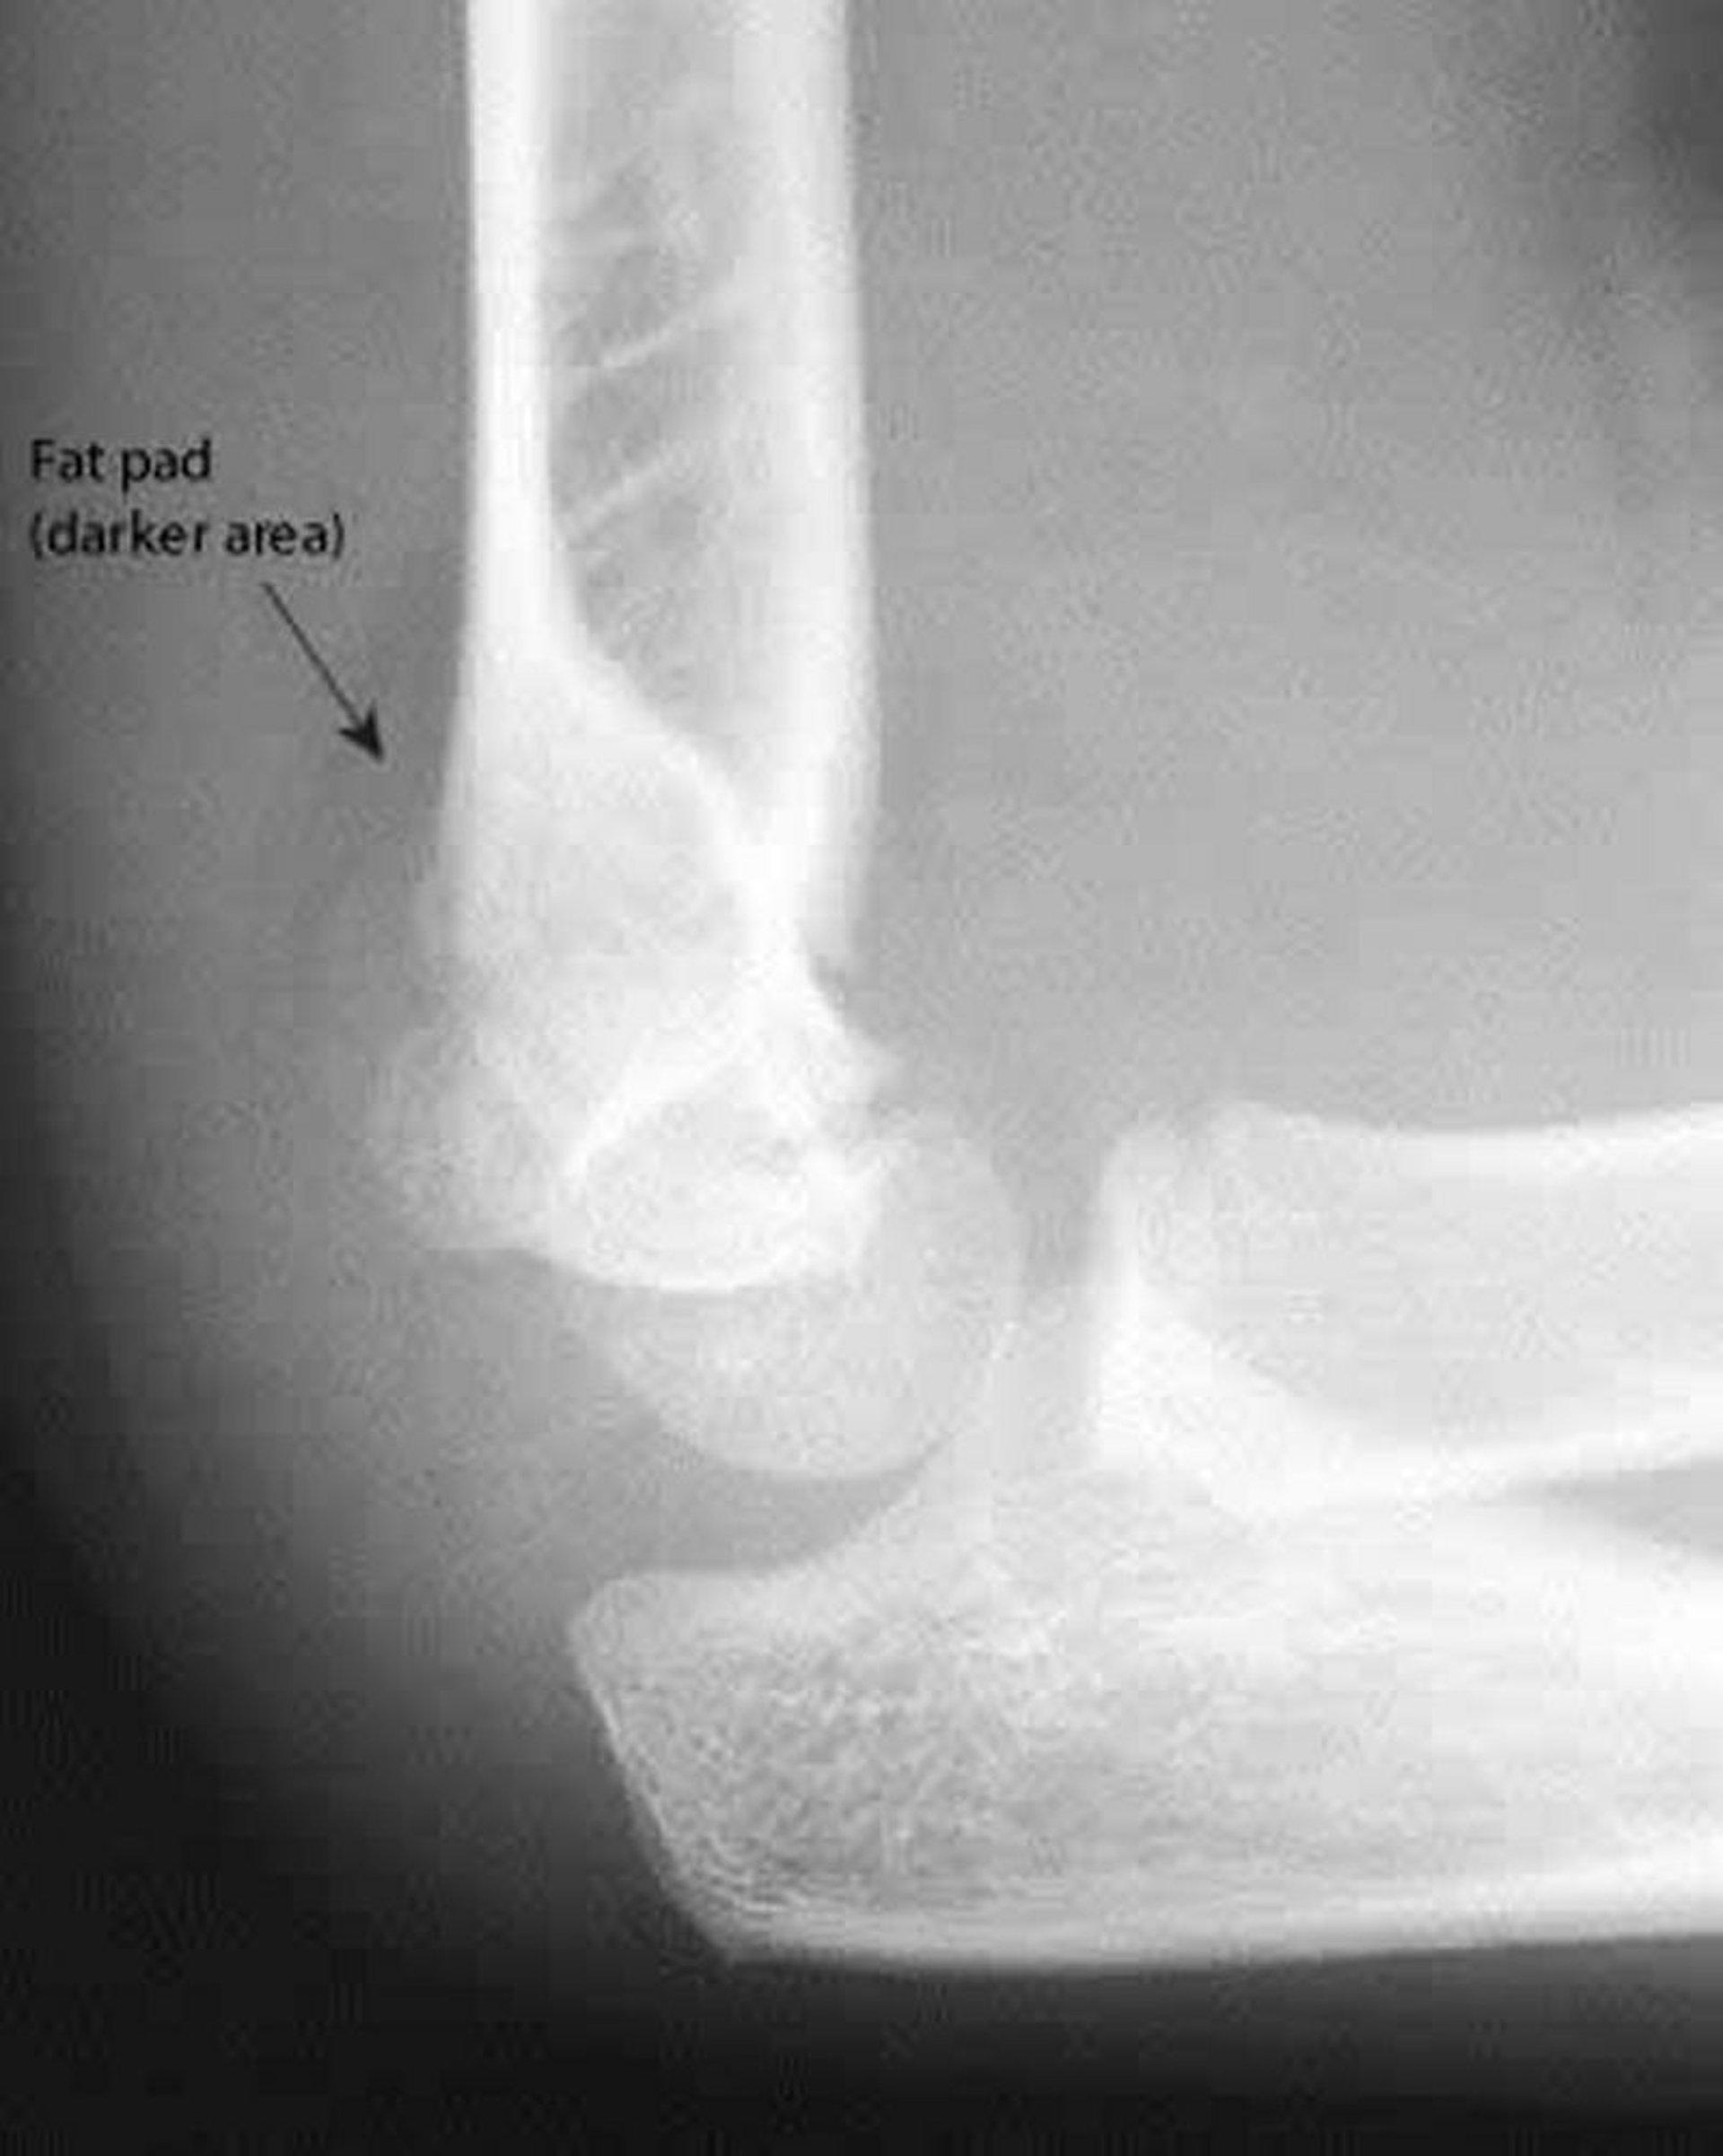

Задняя жировая подушка

Задняя жировая подушка всегда свидетельствует о патологии. Также на этой рентгенограмме передняя плечевая линия не проходит через середину головчатого возвышения плечевой кости.

Image courtesy of Danielle Campagne, MD.